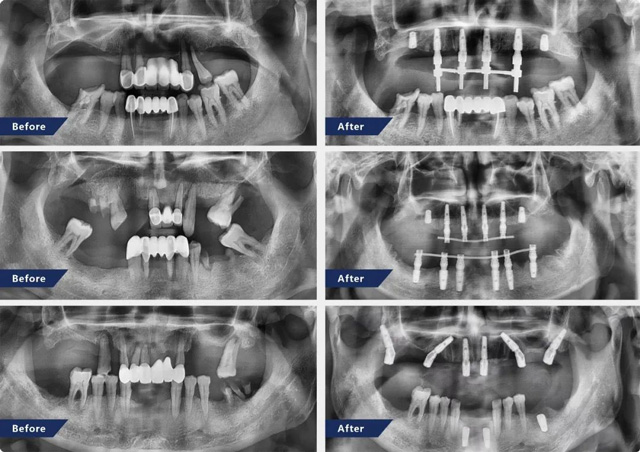

孫濤的朋友圈,曬得最多的就是自己做的半口全口種植案例,每一張圖都是他自豪的作品,是他成就感的來源。孫濤有“對稱型”強迫癥,生活中體現在物品必須對稱或整齊,延伸到工作中,就是對植體植入“精準度”的極致追求。每次手術前,他習慣專門抽出一段時間,看著顧客的口腔術前片冥想手術過程,直到胸有成竹。手術結束后,他細細分析每顆植體植入的位置是否和設計方案一致,“我的自我要求是,偏差只能有1~2mm,自由手種植要像數字化導板種植一樣精準。”截至目前,孫濤在新橋口腔完成了逾10000顆種植牙治療,其中半口全口即刻種植近千例。